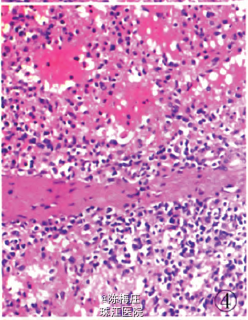

初步诊断:子宫肌瘤,子宫腺肌病,盆腔多发肿物性质待查。 确定诊断:盆腔腹膜脾组织植入。 完善相关检查,行全子宫切除术。病理检查:眼观:全切子宫1个,13 cm×8 cm×5.5 cm大小,子宫做多个切面,在肌层内查见2个大小不等灰白色肌瘤,肌瘤面积O.3 em×0.2 cm—l cm×0.66cm,肌瘤切面质韧,灰白色,呈编织状,边界清;内膜光滑,厚0.2—0.3 em,肌层厚2.5—3.5 cm,部分呈海绵状,子宫颈光滑,切面质韧,质地较细。盆腔内不规则肿物1个,灰红色,表面结节状,11cm×7.5 cm×3.5 cm大小,做多个切面,切面见多个结节,结节面积:0.4cm×0.3 cm~4.3 cm×2.5 cm,结节切面质脆,灰红色,质地细,结节边界清。另送圆形结节5个,直径1~3 cm不等,切面性质同盆腔较大肿物,均有包膜(图1)。镜检:患者子宫检查为子宫肌瘤,子宫腺肌病,病变无特殊性。盆腔多个肿物病变性质基本一致,为扩张血窦样组织,窦腔内充满红细胞,似脾红髓淤血(图2),在血窦样组织间有大小不等、发育良莠不齐的白髓样结节,结节较大者有小中央动脉(图3),结节较小者中央动脉不明显,内皮细胞无异型性,细胞分化均无异性,无病理性分裂象。可见玻璃变性纤维结缔组织似脾小梁样结构(图4)。免疫表型:血窦样内皮细胞nFli-1强阳性(图5),CD31弱阳性;CD34肿物小血管强阳性而血窦内皮细胞阴性(图6),CR和SMA均阴性;Ki-67增殖指数为5%。